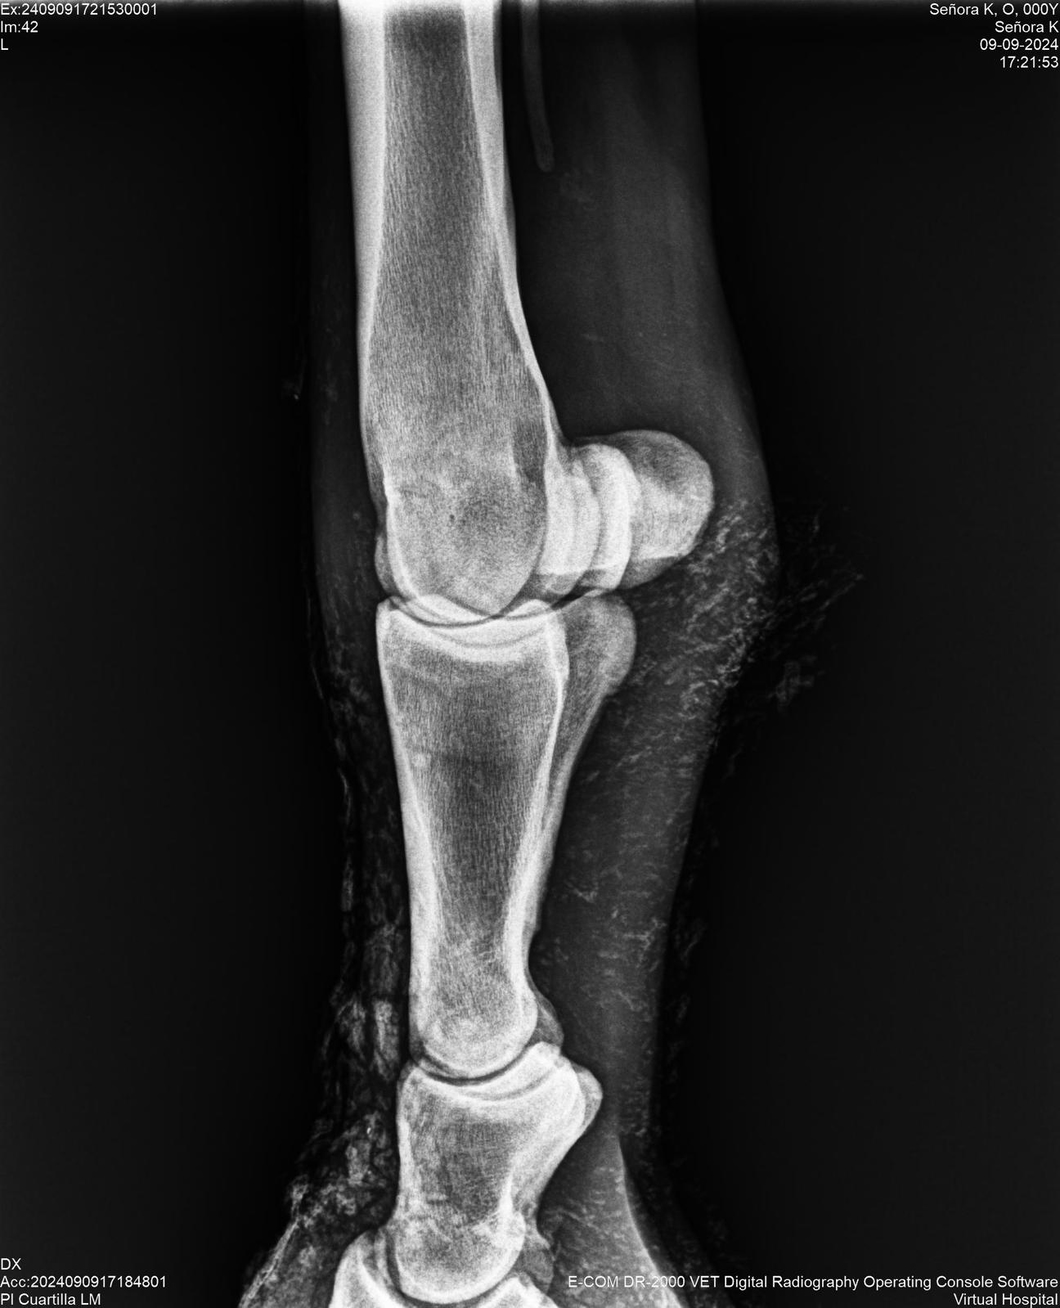

LOTE 44, SEÑORA K

Identificador: #291147-

Generacion 2022